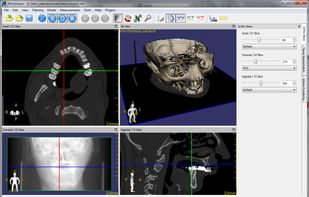

Weasis is a multipurpose standalone and web-based DICOM viewer with a highly modular architecture. It is a very popular clinical viewer used in healthcare by hospitals, health networks, multicenter research trials, and patients.

Weasis is a multipurpose standalone and web-based DICOM viewer with a highly modular architecture. It is a very popular clinical viewer used in healthcare by hospitals, health networks, multicenter research trials, and patients.